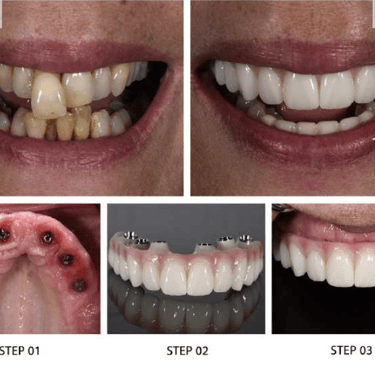

Our Signature Implant Services

Restoring Smiles with Precision and Care

At Dr. Wadkar’s Dental Clinic, we specialize in replacing missing teeth with solutions that look, feel, and function exactly like natural teeth. Using the latest Digital Implant Workflow, we ensure every procedure is minimally invasive and highly predictable.

1. Single & Multiple Tooth Implants

Whether you are missing one tooth or several, we provide customized titanium or zirconia implants. Our approach focuses on preserving your natural bone structure and neighboring teeth.

● The Benefit: No need to grind down healthy adjacent teeth as required for traditional bridges.

2. Full Mouth Rehabilitation

For patients with significant tooth loss, we offer comprehensive full-arch restorations. Utilizing techniques learned from masters, we stabilize your entire smile with a few strategically placed implants.

● The Benefit: Eat what you want, speak clearly, and look years younger with a stable, permanent smile.